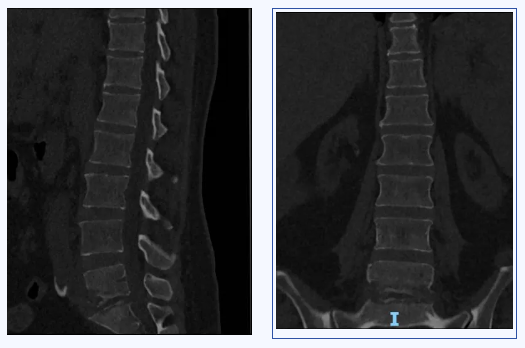

脊柱微创外科在粤西拥有最专业的脊柱感染、脊柱创伤、脊柱退变、脊柱肿瘤及脊柱畸形诊疗团队。患者既往有“慢性肾衰竭(尿毒症期)、甲状旁腺功能亢进、高血压病3级(极高危)、贫血”等疾病,面对复杂的病情,魏波主任和胡资兵教授在患者入院后迅速为其完善检查。抽血结果显示感染指标明显升高,腰椎CT、增强MRI显示腰5、骶1椎体、椎旁及左侧背部软组织异常信号并明显增强,考虑感染性病变。胡资兵教授团队迅速诊断患者为“化脓性脊柱炎”,并积极为患者施行手术治疗做准备。

患者感染病灶位于腰5、骶1,骶1骨质破坏,置入椎弓根钉强度欠佳,容易松动、拔钉,导致内固定失败。传统使用髂骨螺钉替代骶1椎弓根钉,但髂骨螺钉存在钉尾突兀刺激皮肤、与近端腰椎椎弓根钉不在同一纵线、连接困难等缺点。鉴于脊柱微创外科团队过去已在美敦力S7系统辅助下成功完成多例精准导航脊柱外科手术,胡资兵教授团队在征得患者及家属同意后,决定采用“C臂导航下经后路腰5、骶1感染病灶清除、椎管减压、S2AI螺钉、腰椎椎弓根钉棒内固定术”来解决此难题。

S2AI为经骶2骶髂螺钉,置入后与近端腰椎椎弓根钉保持在同一纵线上,连接方便,而且不存在钉尾突兀刺激皮肤的问题,近年来已成为备受推崇的腰骶固定方式,但一直以来S2AI螺钉的置入都极具挑战性。此例患者软组织丰厚,腰骶段暴露困难,更加大了置钉难度。C臂导航对S2AI置入的准确度和安全性具有非常明显的优势,大大降低了以往仅仅根据术者经验完成手术的风险,实现了数字化、精准化的质的飞跃。在清晰的图像指引下,经过3小时的精细操作,成功为这位病情复杂的患者施行了手术。整个手术过程出血量少,S2AI螺钉置入精准,病灶清除彻底。术后患者顺利康复。